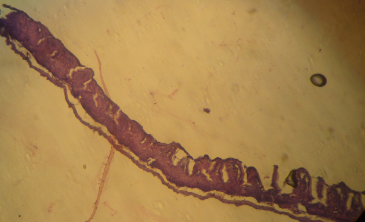

Histology of the intestinal mucosa of Positive control groups

Positive control groups are mice that continue receiving a standard feed and water after being immunized with the native β-Lg or α-La.

The intestinal mucosa of positive control mice has a very pronounced atrophy, characterized by flattened villi limited by a pseudo-stratified epithelium with dystrophic nucleus cubic cells. At the Lamina propria level, the inflammation is very pronounced (Figure 4, Figure 5).

Fig. 4: Microscopic observations of intestinal biopsies of positive control group: mice immunized with the β-Lg.

Intestinal villi are shortened, deformed and expanded; they are bordered by a stratified epithelium. The lymphocytic infiltration in the lamina propria is dense.

The intestinal mucosa of positive control group has a very pronounced atrophy. It is characterized by flattened villi limited by a pseudo-stratified epithelium having dystrophic nucleus cubic cells. At the Lamina propria level, the inflammation is very pronounced.